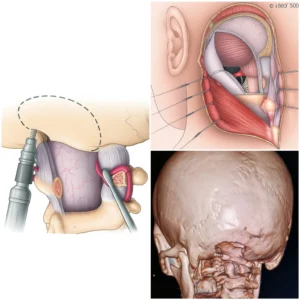

Операциядан кейинги натижа

Операциядан кейин бемор марказ мутахассислари назоратида динамик кузатувда бўлди. Эрта операциядан кейинги даврда қуйидагилар қайд этилди:

- неврологик симптоматиканинг камайиши;

- ҳаракат функцияларининг тикланиши;

- ҳаёт сифатининг яхшиланиши;

- жиддий асоратларнинг йўқлиги.

Назорат МРТ ўтказилган аралашувнинг радикаллигини тасдиқлади.

Ўсма олиб ташланганидан кейин МРТ